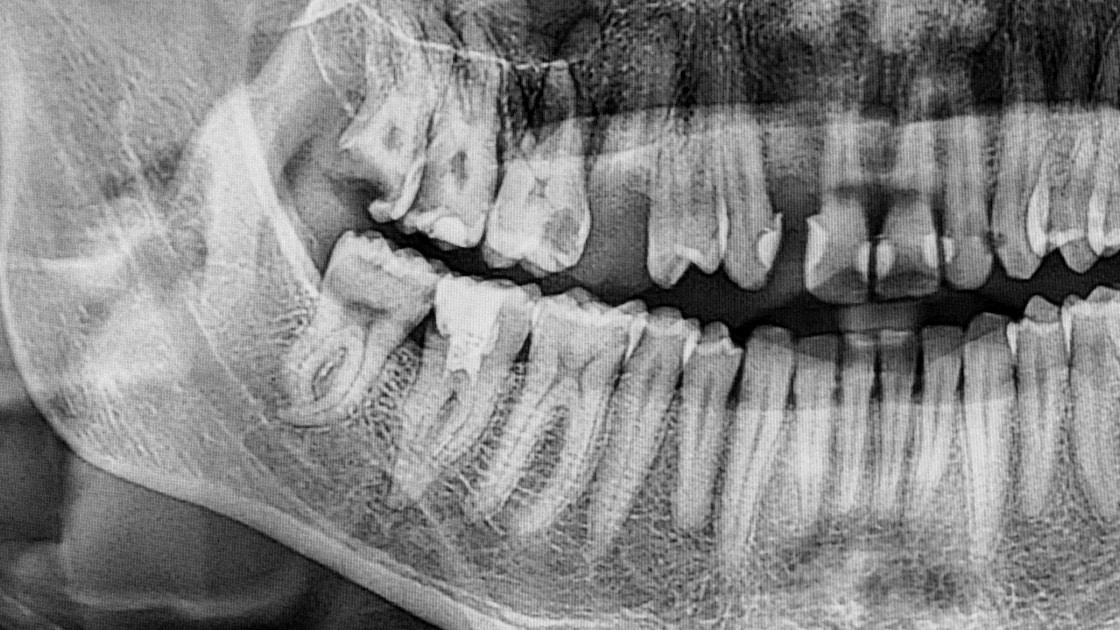

Tooth resorption is a condition where the body begins to break down and absorb the structure of a tooth—often starting from the inside (internal resorption) or the outside (external resorption). This process is abnormal and can lead to serious damage if not treated early.

● Irregular shape or shadow on X-rays

As endodontic specialists, we use advanced imaging like 3D CBCT scans to detect and evaluate the extent of resorption. Treatment may involve: